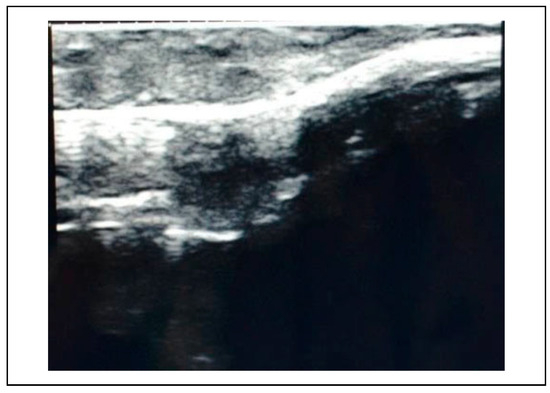

Figure 5.

Preoperative USG—zygomatic buttress.

The subjects of the study group underwent an ultrasonographic examination before reduction at the frontozygomatic region, infraorbital rim and zygomatic buttress to assess the discontinuity of the bony fractured margins which were surface marked using a dermi marker at the respective points (Figure 3, Figure 4, Figure 5). These points served as landmarks to assess the reduction of the fracture site post reduction and fixation.